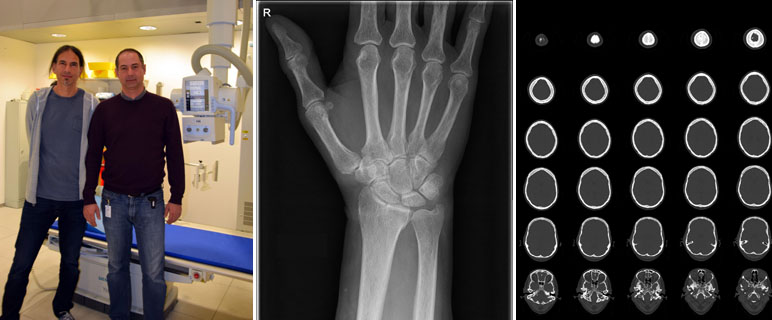

Das Department Radiologie wurde für die hohen Qualitätsstandards insbesondere im Strahlenschutz ausgezeichnet: Derzeit sind die Innsbrucker Univ.-Kliniken für Radiologie und Neuroradiologie die beiden einzigen in Österreich, die von der Europäischen Gesellschaft für Radiologie im Rahmen der“ EuroSafe Imaging Stars“-Kampagne mit fünf Sternen ausgezeichnet wurde. Das Department Radiologie nimmt damit eine Vorbildfunktion ein. Weitere Einrichtungen werden dem Beispiel Innsbruck folgen.

Die EuroSafe Imaging Initiative der Europäischen Gesellschaft für Radiologie (ESR, European Society of Radiology) wurde 2014 gestartet, um den Strahlenschutz im medizinischen Bereich zu forcieren und zu verbessern. Neben der Optimierung der Untersuchungen und der Bildqualität zielt die Initiative auch auf die Verbesserung der Kommunikation zwischen Patient:innen und medizinischen Personal ab. Im Rahmen der Überprüfung der EuroSafeImaging-Qualitätskriterien hat das Department Radiologie der Medizinischen Universität Innsbruck die höchst mögliche Punktzahl (fünf Sterne) erhalten. Die beiden zum Department gehörenden Kliniken werden von Univ.-Prof.in Dr.in Elke Gizewski (Neuroradiologie) und o.Univ.-Prof. Dr. Werner Jaschke (Radiologie) geleitet.

Die hervorragende Bewertung ist eine Auszeichnung für die seit Jahren gesetzten Maßnahmen zur Qualitätssicherung und -kontrolle. Ein wichtiges Ziel ist der sichere Umgang mit der verwendeten Strahlung und nach Möglichkeit eine Weiterentwicklung der verwendeten Technik zur Reduzierung der verwendeten Dosis. Patient:innen erhalten die höchstmögliche Sicherheit. „Der erste Schritt zur Dosisreduzierung ist die genaue Dokumentation der verwendeten Strahlenintensität. Nur wenn wir die Dosis genau kennen, können wir auch Maßnahmen zur Optimierung setzen“, erklären Dr. Michael Verius und Mag. Pavle Torbica. Die beiden Medizinphysiker sind die Strahlenschutzbeauftragten am Department Radiologie. Gemeinsam mit ihrem Kollegen Mag. Robert Eder haben sie eine Software entwickelt, die bereits seit Mitte 2012 angewendet und laufend verbessert wird. „Damit können wir für jede Patientin und jeden Patienten die verwendete Strahlendosis erfassen, speichern und analysieren“, erklärt Michael Verius. Damit nimmt das Department Radiologie eine Vorreiterrolle in Bezug auf das Dosis-Management in Österreich ein. „Für die behandelnden Ärzt:innen ermöglicht die Datenerfassung es frühzeitig zu erkennen, wenn vorgeschriebene Belastungshöchstgrenzen überschritten werden“, sagt Pavle Torbica. Die erfassten Daten sind auch relevant für die Weiterentwicklung auf dem Gebiet der Radiologie. Im Rahmen von Forschungsprojekten werden die Werte analysiert. Die Erkenntnisse sollen dabei helfen, die Strahlendosis bei einer Untersuchung oder Behandlung weiter zu optimieren, ohne die Bildqualität zu verschlechtern. Insbesondere im Bereich der Computertomographie (CT) sind hier noch weitere Verbesserungen möglich. „CT-Untersuchungen machen zwar nur 9 bis 10 Prozent aller Untersuchungen aus. Ihr Anteil an der Kollektivdosis beträgt aber trotzdem 65 bis 70 Prozent“, weiß Michael Verius. Ähnliches gilt für durchleuchtungsgesteuerte therapeutische Eingriffe wie z. B. die katheterbasierte Behandlung von Gefäßerkrankungen.